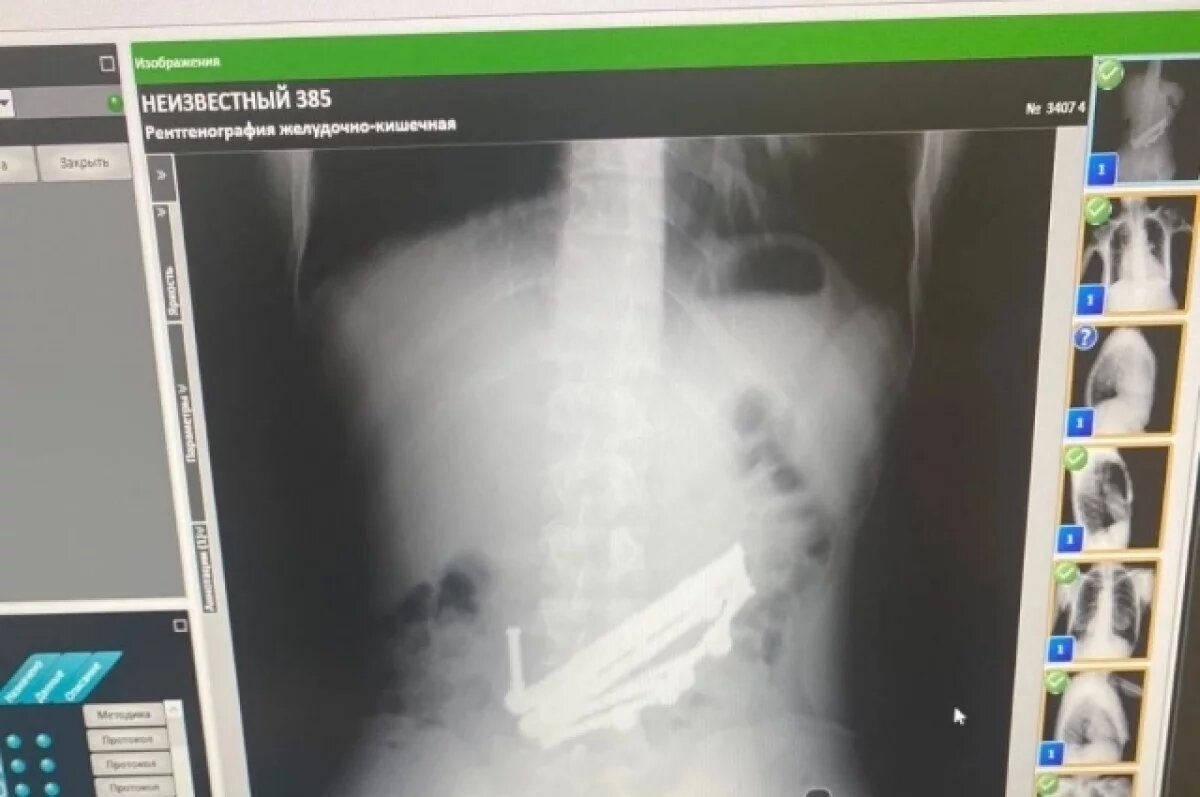

Рентген показал наличие металла.

Скорую вызвали родители парня. В больнице ему сделали рентген, который показал наличие металла в желудке и кишечнике.

Операция по спасению этого пациента длилась более двух часов. За это время хирурги ВКБ № 4 извлекли из желудка и кишечника молодого человека более десятка деталей магнитного конструктора. Их общий вес составил 420 граммов.